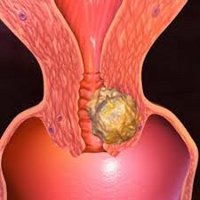

Рак шейки матки

Рак шейки матки – опухолевое поражение нижнего отдела матки, характеризующееся злокачественной трансформацией покровного эпителия (экто- или эндоцервикса). Специфическим проявлениям рака шейки матки предшествует бессимптомное течение; в дальнейшем появляются контактные и межменструальные кровянистые выделения, боли в животе и крестце, отеки нижних конечностей, нарушения мочеиспускания и дефекации. Диагностика при раке шейки матки включает проведение осмотра в зеркалах, расширенной кольпоскопии, исследования цитологического соскоба, биопсии с гистологическим заключением, эндоцервикального кюретажа. Лечение рака шейки матки проводят с учетом гистологической формы и распространенности с помощью хирургического вмешательства, лучевой терапии, химиотерапии или их комбинации.

Классификация

По гистологическому типу, в соответствии с двумя видами эпителия, выстилающего шейку матки, различают плоскоклеточный цервикальный рак с локализацией в эктоцервиксе (85-95%) и аденокарциному, развивающуюся из эндоцервикса (5-15%). Плоскоклеточный рак шейки матки, в зависимости от степени дифференцировки, может быть ороговевающим, неороговевающим и низкодифференцированным. К редким гистотипам рака шейки матки относятся светлоклеточная, мелкоклеточная, мукоэпидермоидная и др. формы. С учетом типа роста различают экзофитные формы рака шейки матки и эндофитные, встречающиеся реже и имеющие худший прогноз.

Симптомы рака шейки матки

Клинические проявления при карциноме in situ и микроинвазивном раке шейки матки отсутствуют. Появление жалоб и симптоматики свидетельствует о прогрессировании опухолевой инвазии. Наиболее характерным проявлением рака шейки матки служат кровянистые выделения и кровотечения: межменструальные, постменопаузальные, контактные (после полового акта, осмотра гинекологом, спринцевания и т. д.), меноррагии. Больные отмечают появление белей — жидких, водянистых, желтоватого или прозрачного цвета влагалищных выделений, обусловленных лимфореей. При распаде раковой опухоли выделения принимают гноевидных характер, иногда имеют цвет «мясных помоев» и зловонный запах.

При прорастании опухоли в стенки таза или нервные сплетения появляются боли в животе, под лоном, в крестце в покое или во время полового акта. В случае метастазирования рака шейки матки в тазовые лимфоузлы и сдавливания венозных сосудов могут наблюдаться отеки ног и наружных гениталий.

- Осмотр шейки матки в зеркалах. Визуальный гинекологический осмотр в ранней стадии позволяет обнаружить или заподозрить РШМ по внешнем признакам: изъязвлениям, изменению окраски шейки матки. В инвазивной стадии при экзофитном типе роста рака на поверхности шейки матки определяются фибринозные наложения, опухолевидные разрастания красноватого, белесоватого, розовато-серого цвета, которые легко кровоточат при прикосновении. В случае эндофитного роста цервикального рака шейка становится увеличенной, приобретает бочковидную форму, неровную бугристую поверхность, неравномерную розово-мраморную окраску. При ректо-вагинальном исследовании в параметрии и малом тазу могут определяться инфильтраты.